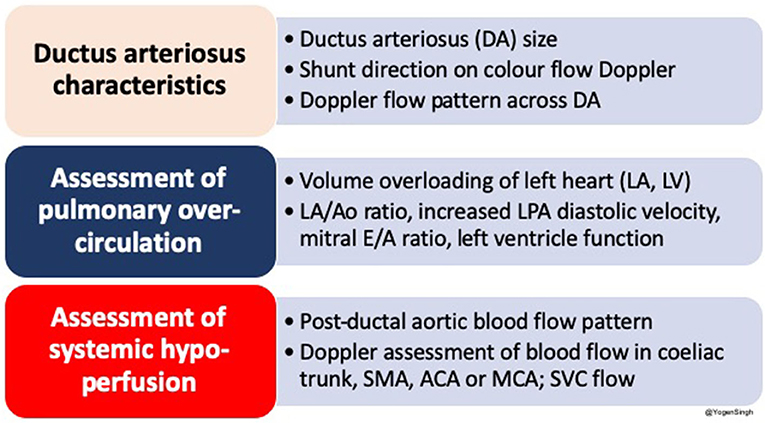

The echocardiography is the gold standard bedside investigation to diagnose PDA. In addition to make a confirmative diagnosis of PDA and exclude/diagnose any associated congenital heart defect (CHD), it can help in estimating the magnitude of shunt volume and assessing its hemodynamic significance—it can be used to assess the hemodynamic impact from pulmonary overcirculation and systemic hypoperfusion due to shunt volume (13–15). This could be systematically achieved by studying: (a) ductal characteristics, (b) parameters of pulmonary overcirculation, and (c) signs of systemic hypoperfusion (Figure 2).

Figure 2. Summary of an approach to echocardiographic assessment of PDA and hemodynamic evaluation; LA, left atrium; LV, left ventricle; DA, ductus arteriosus; Ao, aorta; SMA, superior mesenteric artery; ACA, anterior cerebral artery; MCA, middle cerebral artery; SVC, superior vena cava.